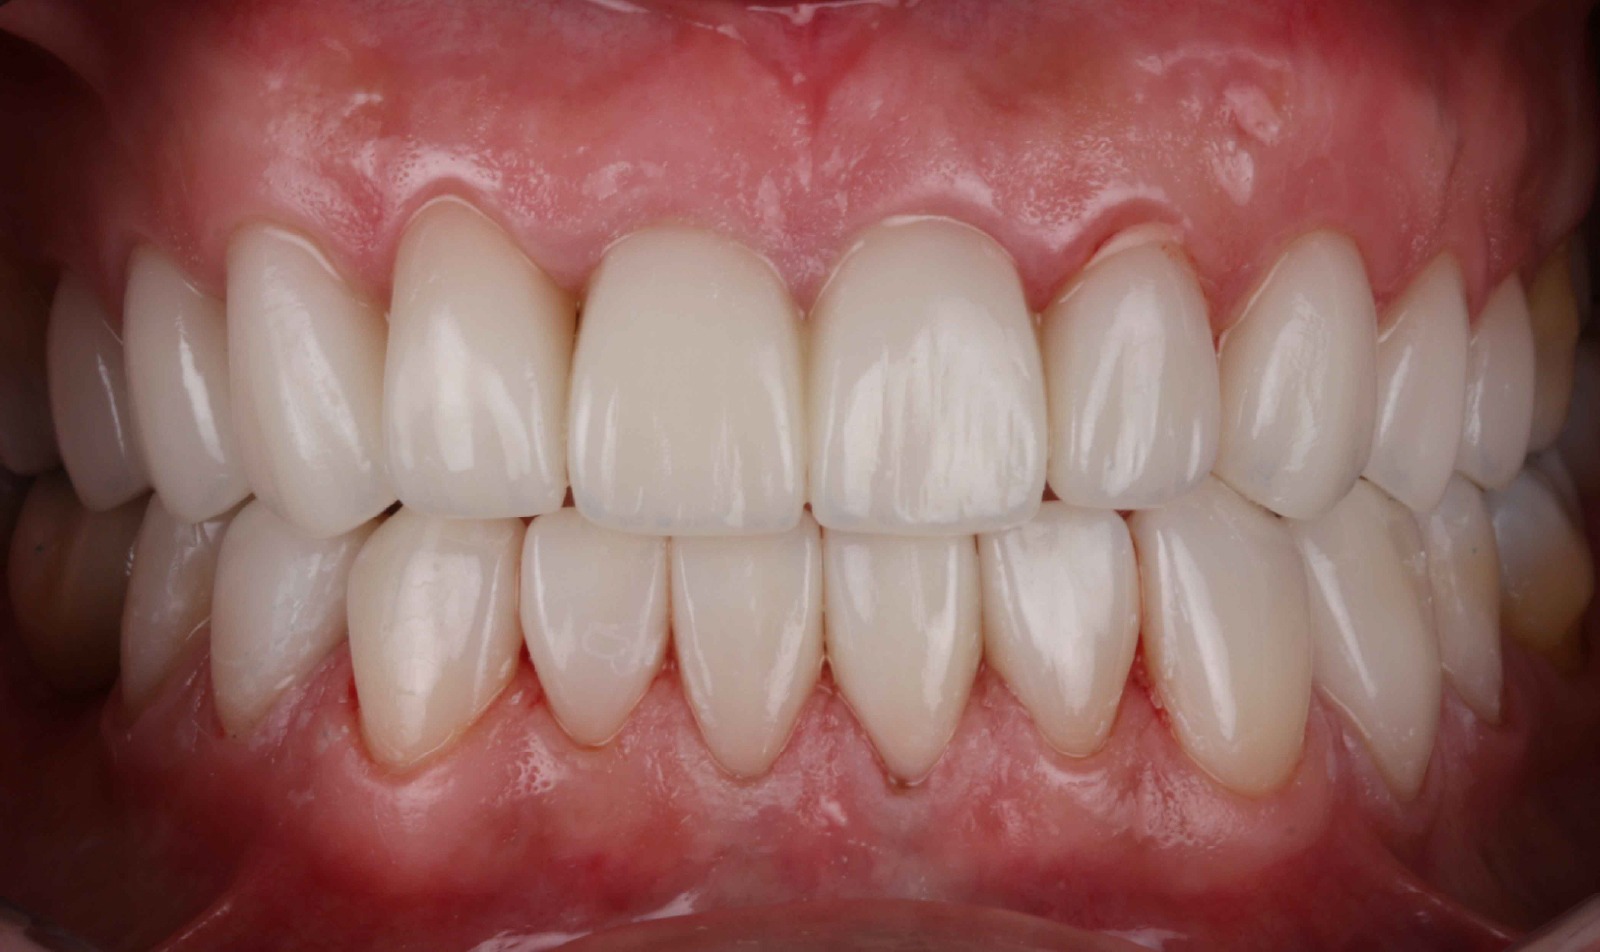

Injerto de encía para solucionar recesión

BeforeAfter